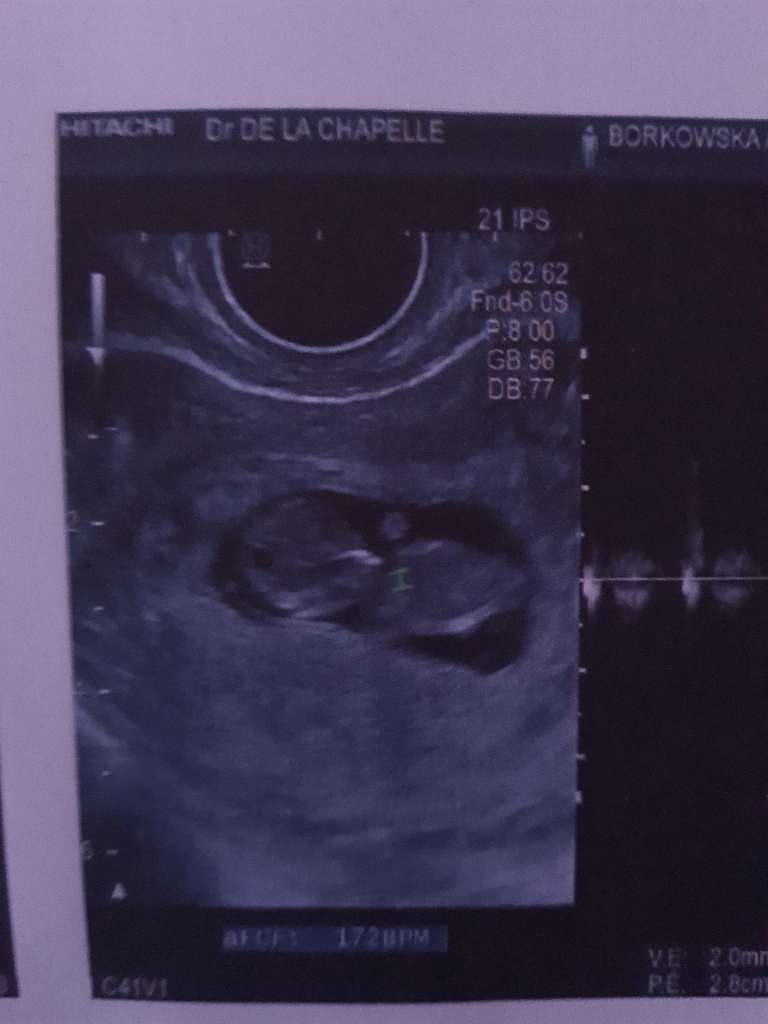

Miałam podoba sytuację wczoraj w nocy, szpital, USG, bobas i cała reszta w porządku, nie wiadomo, skąd to krwawienie. Może po prostu pękło naczynko. W poniedziałek mam kontrolę, biorę dupka i na szczęście już nie krwawie ☺

9+5To super bardziej się cieszę że u Ciebie też się to skończyło tylko na strachuu mnie lekarz nic mi nie dał na podtrzymanie. Powiedziała że na tym etapie albo ciąża się utrzymać albo nie. A który tydzien u ciebie ?